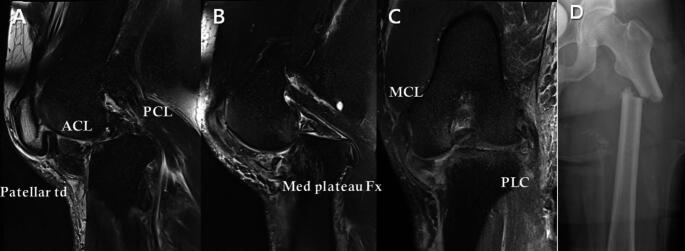

Methods: We retrospectively identified 100 patients (115 knees) with MLKIs and/or dislocations at our trauma center between 2007 and 2021. Magnetic resonance imaging was routinely performed to evaluate the injured structures and extent of injury. The anatomic structures of the knee were categorized into anterior and posterior cruciate ligaments (ACL, PCL) and medial and posterolateral structures, and further classified according to the modified Schenck classification. The study participants were divided into two groups: 40 and 75 knees classified as MLKI with and without dislocation, respectively.

Results: MLKIs with dislocations showed 13% (5/40 knees) and 18% (7/40 knees) incidence, whereas MLKIs without dislocation showed 15% (11/75 knees) and 13% (10/75 knees) incidence of medial and lateral meniscal tears respectively. The two groups also had a significant discrepancy in the patterns of meniscal tears. For medial meniscal tears, radial tears were more prevalent in MLKIs with dislocation, and longitudinal tears in MLKIs without dislocation (p = 0.197). For lateral meniscal tears, anterior horn or totally detached tears were more prevalent in MLKIs with dislocation, and radial tears in MLKIs without dislocation (p = 0.026). Additionally, complete rupture of all four major ligaments was found in 38% (15/40 knees) of the cases with dislocation, with the majority showing complete ruptures of both the ACL and PCL. Concomitant serious injuries, such as popliteal artery injury and fractures, were observed only in cases involving high-energy trauma and dislocation.

Conclusions: MLKIs with dislocation show distinct ligament and meniscal injury patterns compared to those without, highlighting the importance of severity and anatomical classification in diagnosing associated knee injuries.